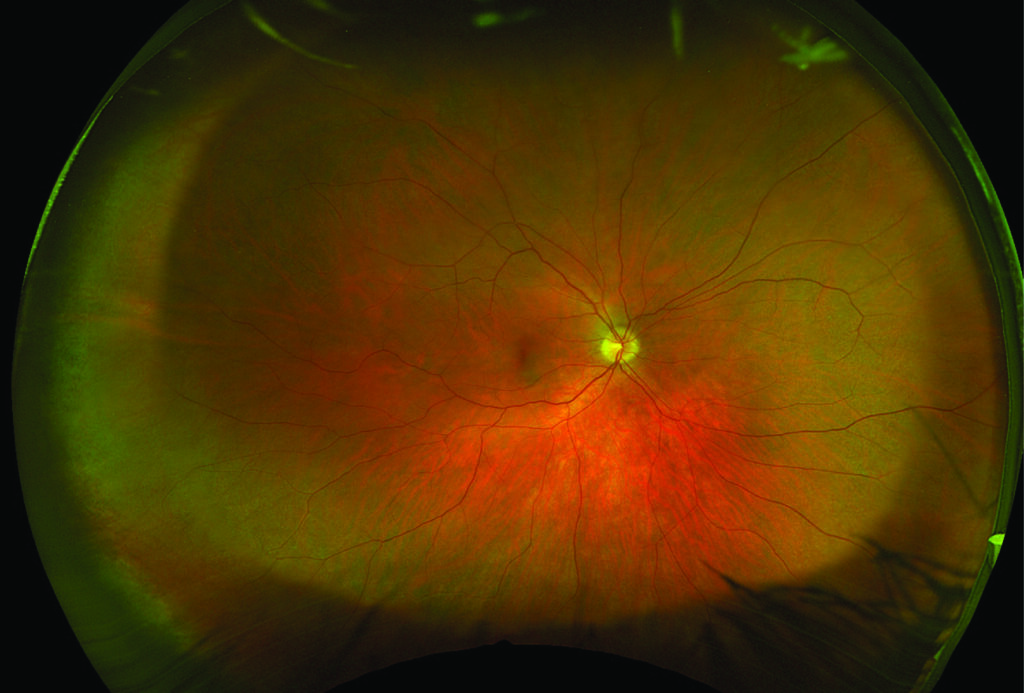

What is a retinal photograph?

You may need the retina inside your eye photographed at your eye clinic appointment. This will help the doctor look inside your eye and keep an accurate record for any future visits.

Retinal photographs are a very common procedure. Nothing touches your eye, although we may need to gently lift up your eye lids. There is a bright flash as the photograph is taken so please tell the photographer if you have sensitive eyes.